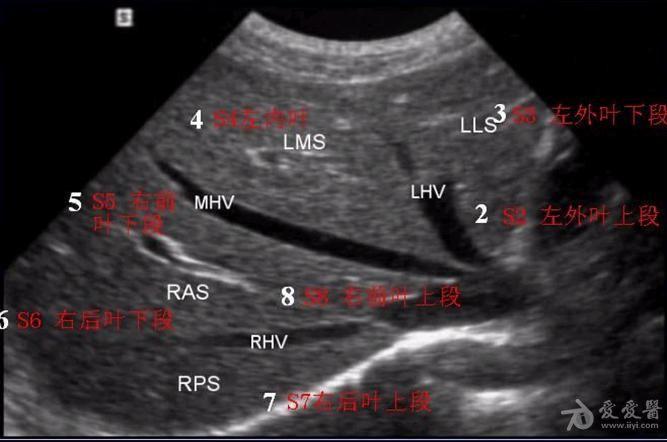

超声肝的分段解剖图片,肝超声分段解剖示意图

肝脏的分叶分段(解剖 超声声像图)

肝脏超声分段

肝超声分段解剖示意图

超声肝脏8分段法图谱